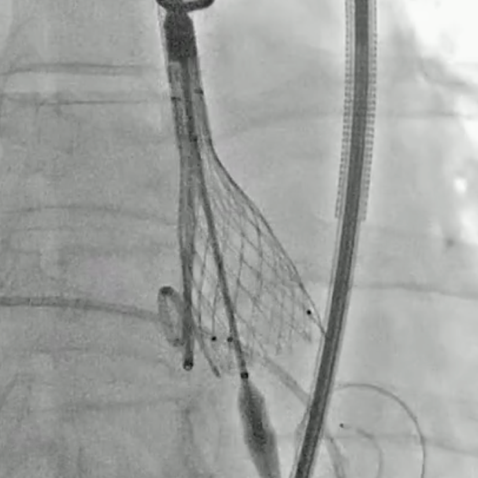

建立股静脉-房间隔-左房-左室-主动脉轨道

行二尖瓣球囊扩张

成功植入TAVR瓣膜